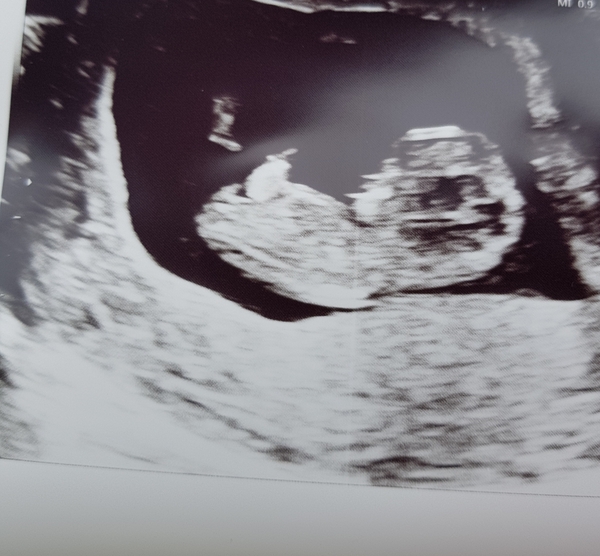

Baby measuring 11 weeks today and wriggling about Smile

Hope yours goes as well @Cakelaur!

MagicalCreatures · 25/05/2018 14:10

Oh Wiggle beautiful picture x

kaytees · 25/05/2018 14:49

Hello baby wiggle @Wiggle4 - you look wonderful!

All is fine. Perfect little bean. Looks like a teddy bear. Measuring a day ahead of schedule at 10+5. 😍🌈

MagicalCreatures · 25/05/2018 17:54

@Cakelaur fantastic news. Oh it does look like a teddy bear. Beautiful little bubba x

Aww cute teddy baby @Cakelaur! Great news Smile